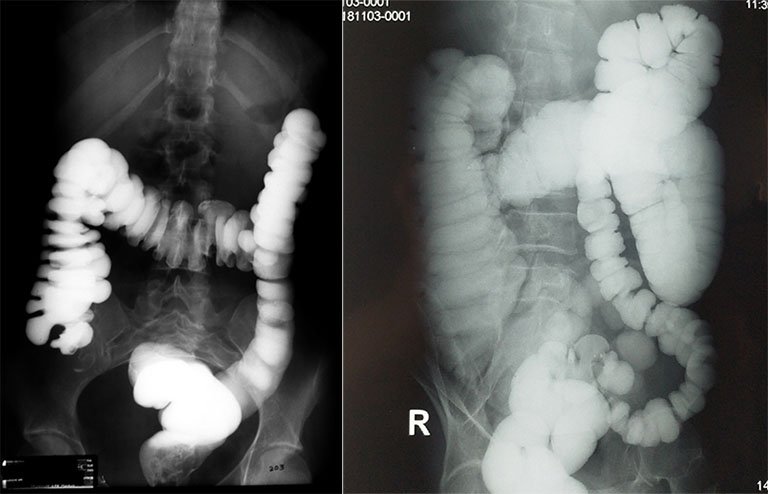

Ung thư đại trực tràng là một bệnh rất thường gặp hiện nay, không chỉ riêng ở các nước phát triển mà cả những quốc gia đang phát triển, trong đó có Việt Nam. Nhìn chung ung thư đại tràng có 3 loại, bao gồm loại gây hẹp tắc đại tràng, loại sùi và loại phát triển trong thành đại tràng. Loại ung thư gây hẹp tắc đại tràng hay gặp thấy ở tại chỗ tiếp nối giữa đại tràng xích ma với trực tràng. Tổn thương là một khối u nhỏ, khiến cho lòng đại tràng bị chít hẹp lại. Khối u ung thư ở đại tràng phải ít khi làm hẹp tắc ruột, ngược lại khối u ở đại tràng trái dù nhỏ nhưng lại có xu hướng làm hẹp lòng đại tràng.

- Rút dây dẫn, sau đó bơm thuốc cản quang tan trong nước giúp đánh giá mức độ và vị trí hẹp.

- Bơm thuốc cản quang qua ống thông để xác định mức độ, vị trí và chiều dài đoạn hẹp.